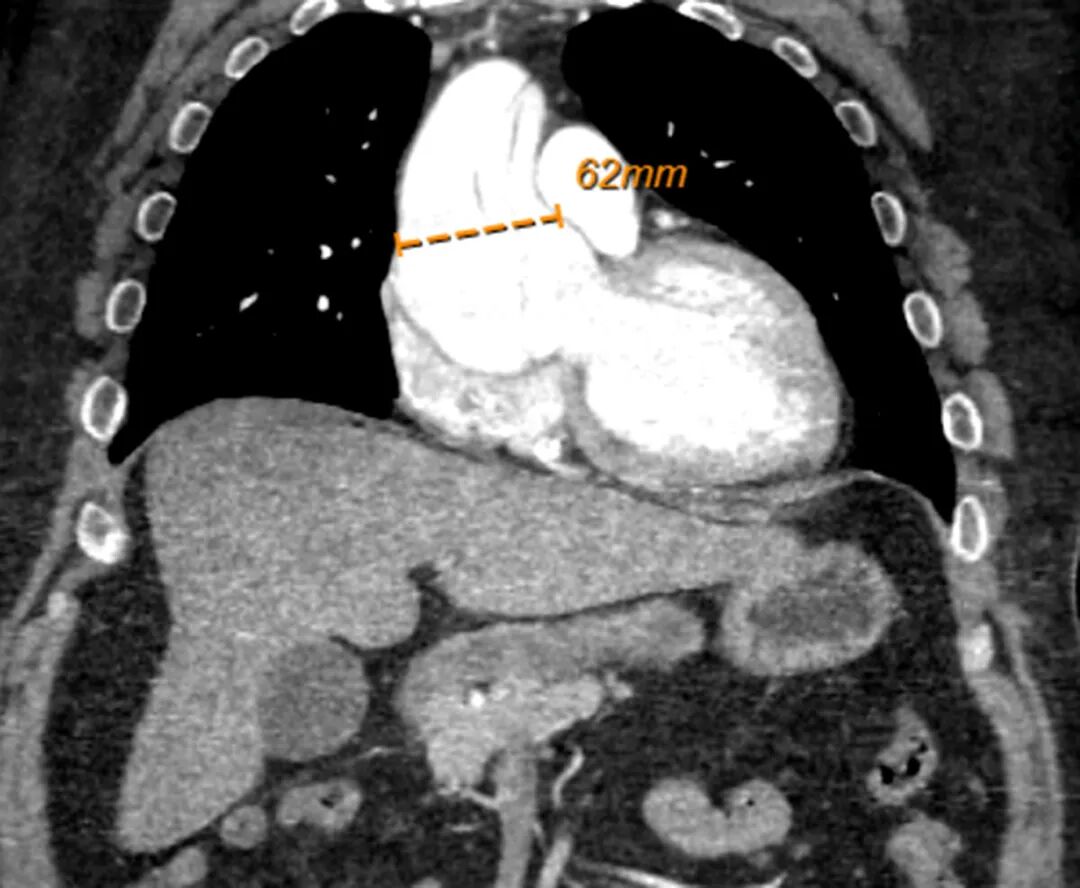

图 4.胸部、腹部和骨盆CT血管造影:冠状视图

CT 血管造影显示主动脉瘤扩张,直径6.2 cm。